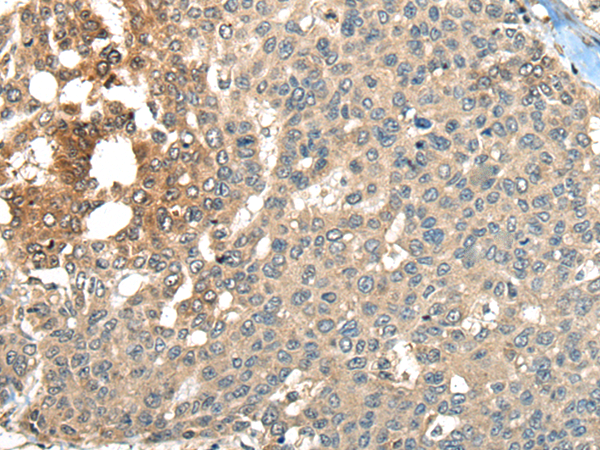

分类: 科研抗体货号: P10831别名: B10, NPP3, PDNP3, CD203c, PD-IBETA应用: IHC反应种属: Human, Mouse, Rat